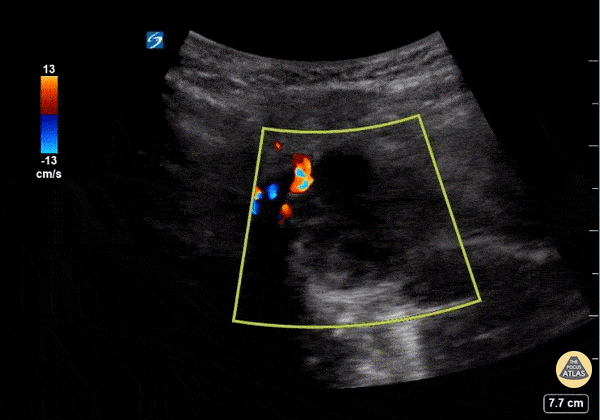

This is a submandibular view of a peritonsillar abscess. Color doppler is used to visualize blood vessels immediately deep to the abscess. By convention, the left side of the screen is posterior and the right side of the screen is anterior. Garrett Ghent, Resuscitationist/Diagnostician; Norfolk, VA @garrettghentMD